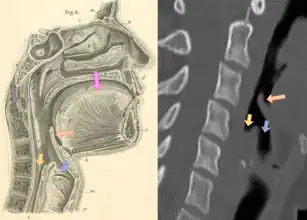

Drawing (left image) and CT scan (right image) of the normal pharynx as a cross-section viewed from the side (sagittal view), including the normal epiglottis (orange arrow), opening to the esophagus (yellow arrow), and opening to the trachea (blue arrow). An infected epiglottis becomes swollen and causes issues with swallowing, speaking, and breathing due to its proximity to the esophagus and trachea. Other labeled structures include the tongue (pink arrow) and vertebral bodies of the cervical spine (grey arrow)